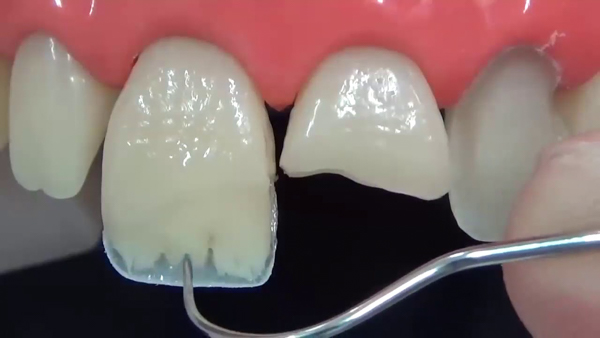

Phương pháp dán sứ cho răng bị mẻ là một kỹ thuật che phủ, bọc lớp mặt dán với độ dày thường từ 0.2 mm – 0.5 mm để che phủ vết mẻ trên răng cửa. Tùy thuộc vào vị trí và mức độ mẻ, mặt dán có thể được sử dụng để che phủ một phần hoặc toàn bộ mặt trước của răng.

So với việc bọc răng sứ, kỹ thuật dán mặt sứ cũng qua các bước tương tự. Tuy nhiên, thay vì mài nhiều, bác sĩ chỉ loại bỏ một phần lớp men răng bên ngoài, giúp thủ tục trở nên đơn giản hơn.

Phương pháp này mang lại vẻ đẹp tự nhiên cho hàm răng và gương mặt, nhờ màu sắc của sứ tương tự như răng thật, khiến người đối diện khó có thể phát hiện. Đồng thời, đây cũng là phương án để khôi phục sự toàn vẹn ban đầu cho răng của bạn. Thời gian thực hiện nhanh chóng và hiệu quả lâu dài là điểm mạnh khiến nhiều người ưa chuộng phương pháp này.